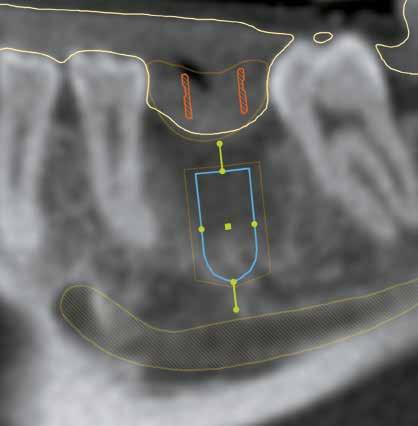

2.a, b, c, d, f ábra: Az implantációs beavatkozás tervezése SMART Guide rendszerrel. Jól látszik az implantátum pozíció mezio-disztális és oro-vesztibuláris metszetben, illetve viszonya a lágyrészekhez, tervezett fogpótláshoz és idegcsatornához.

esetben a rendszer egyik nagy előnye, hogy a teljes képalkotás el tud készülni egyetlen lenyomat alapján. A tervezést így közvetlenül a CBCT elkészülte után elvégeztük. Az automatikusan elvégzett digitális fogfelállítás megfelelő támpontot adott csavarozható koronás protetikai ellátás megtervezéséhez. Az alkalmazott implantációs rendszer alapos irodalmi dokumentációval és több évtizedes múlttal rendelkező prémium rendszer (Straumann Roxolid, SP d:4,1mm, 10mm). Megfelelő mucosa vastagság lehetővé tette “tissue level” implantátum alkalmazását, stabil kötőszövetes tapadást biztosít már az első műtéti fázist követően az implantátum felszínén, kiküszöböli a mikromozgás, valamint ebből következő bakteriális beszűrődés okozta marginális csontlebontódást. Ezen kívül a műtéti fázisokat is lerövidítheti nyitott, illetve félig nyitott (“semi-submerged”) gyógyulás esetén. A sebészi behatolás minimálvazív feltárásban, gerincéli metszés után történt. A lágyrészprezerváció érdekében nem preferáltuk a transzmucosalis technikát. A behelyezés teljes fúrási szekvenciája az implantációs sablonhoz biztosított műtéti protokoll alapján történt a SMART Guide sebészi eszközökkel. Az implantátum behelyezéseét követően annak pozícióját a protokoll szerint visszamértük. A műtét időtartama igen rövid volt, a megfelelő dokumentáció, és folyamatos ellenőrzés ellenére is kb. 30 perc. A kezdetleges alveolus gyógyulás nem biztosított kellő primer stabilitást nyitott gyógyuláshoz (kb 17 Ncm), így zárócsavar került az implantátumba, melyet teljes lebenyzárás követett. A páciens a posztoperatív időszakban CHX szájöblögetőt alkalmazott a műtéti terület tisztán tartására, valamint antibiotikus terápiában részesült a műtét előtt, valamint az azt követő néhány napban. A műtétet követő 3. hónapban megtörtént a gyógyulási csavar behelyezése sebészi beavatkozás nélkül – kizárólag az alacsony kezdeti primer stabilitás miatt, ugyanis az SLActive felszín 2 hónapot követően már terhelhető – melyet 2 hét után követett a protetikai fázis. A műtét pontosságának kiértékeléséhez és vizualizációjához kis térfogatú poszt-operatív CBCT felvételt készítettünk. A pre-operatív CBCT felvételt és műtéti tervet szuperimpozícióval rávetítettük a poszt-operatív műtéti tervre. A CBCT felvételek pontos összeillesztését szürkeségi értékeken alapuló regisztrációval végeztük.